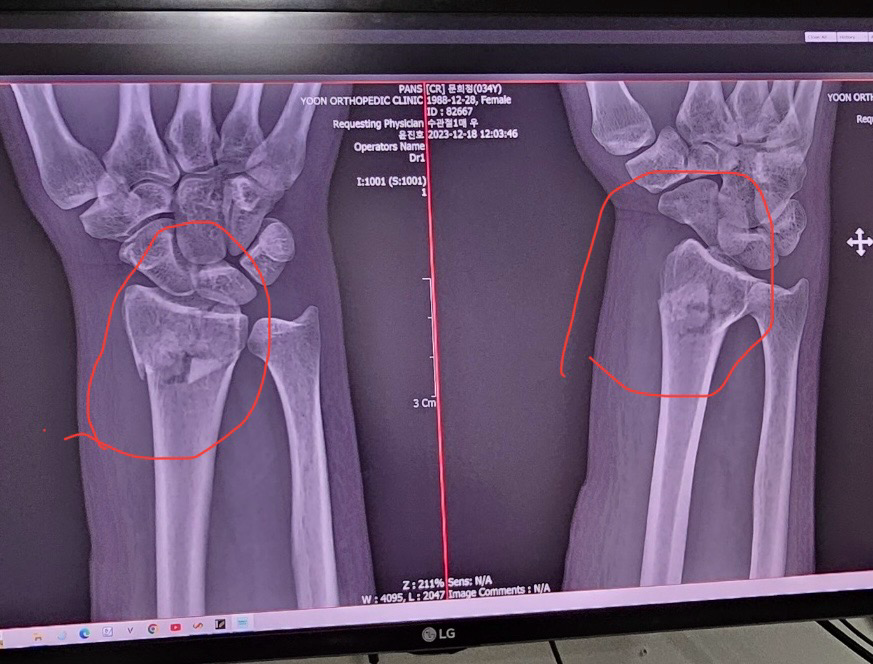

팔목 골절.. 수술 해야할까요?

지난 토요일 눈길에 미끌어져서 주머니 안에 손 넣은 상태에서 짚다가 오른 손목이 골절 되었어요..

이 상태인데 수술 해야될까요

사고 전 손목을 100으로 본다면

*수술안하면 70프로

**수술하면 90프로 이상

돌아온다고 듣고 온 상태 입니다.